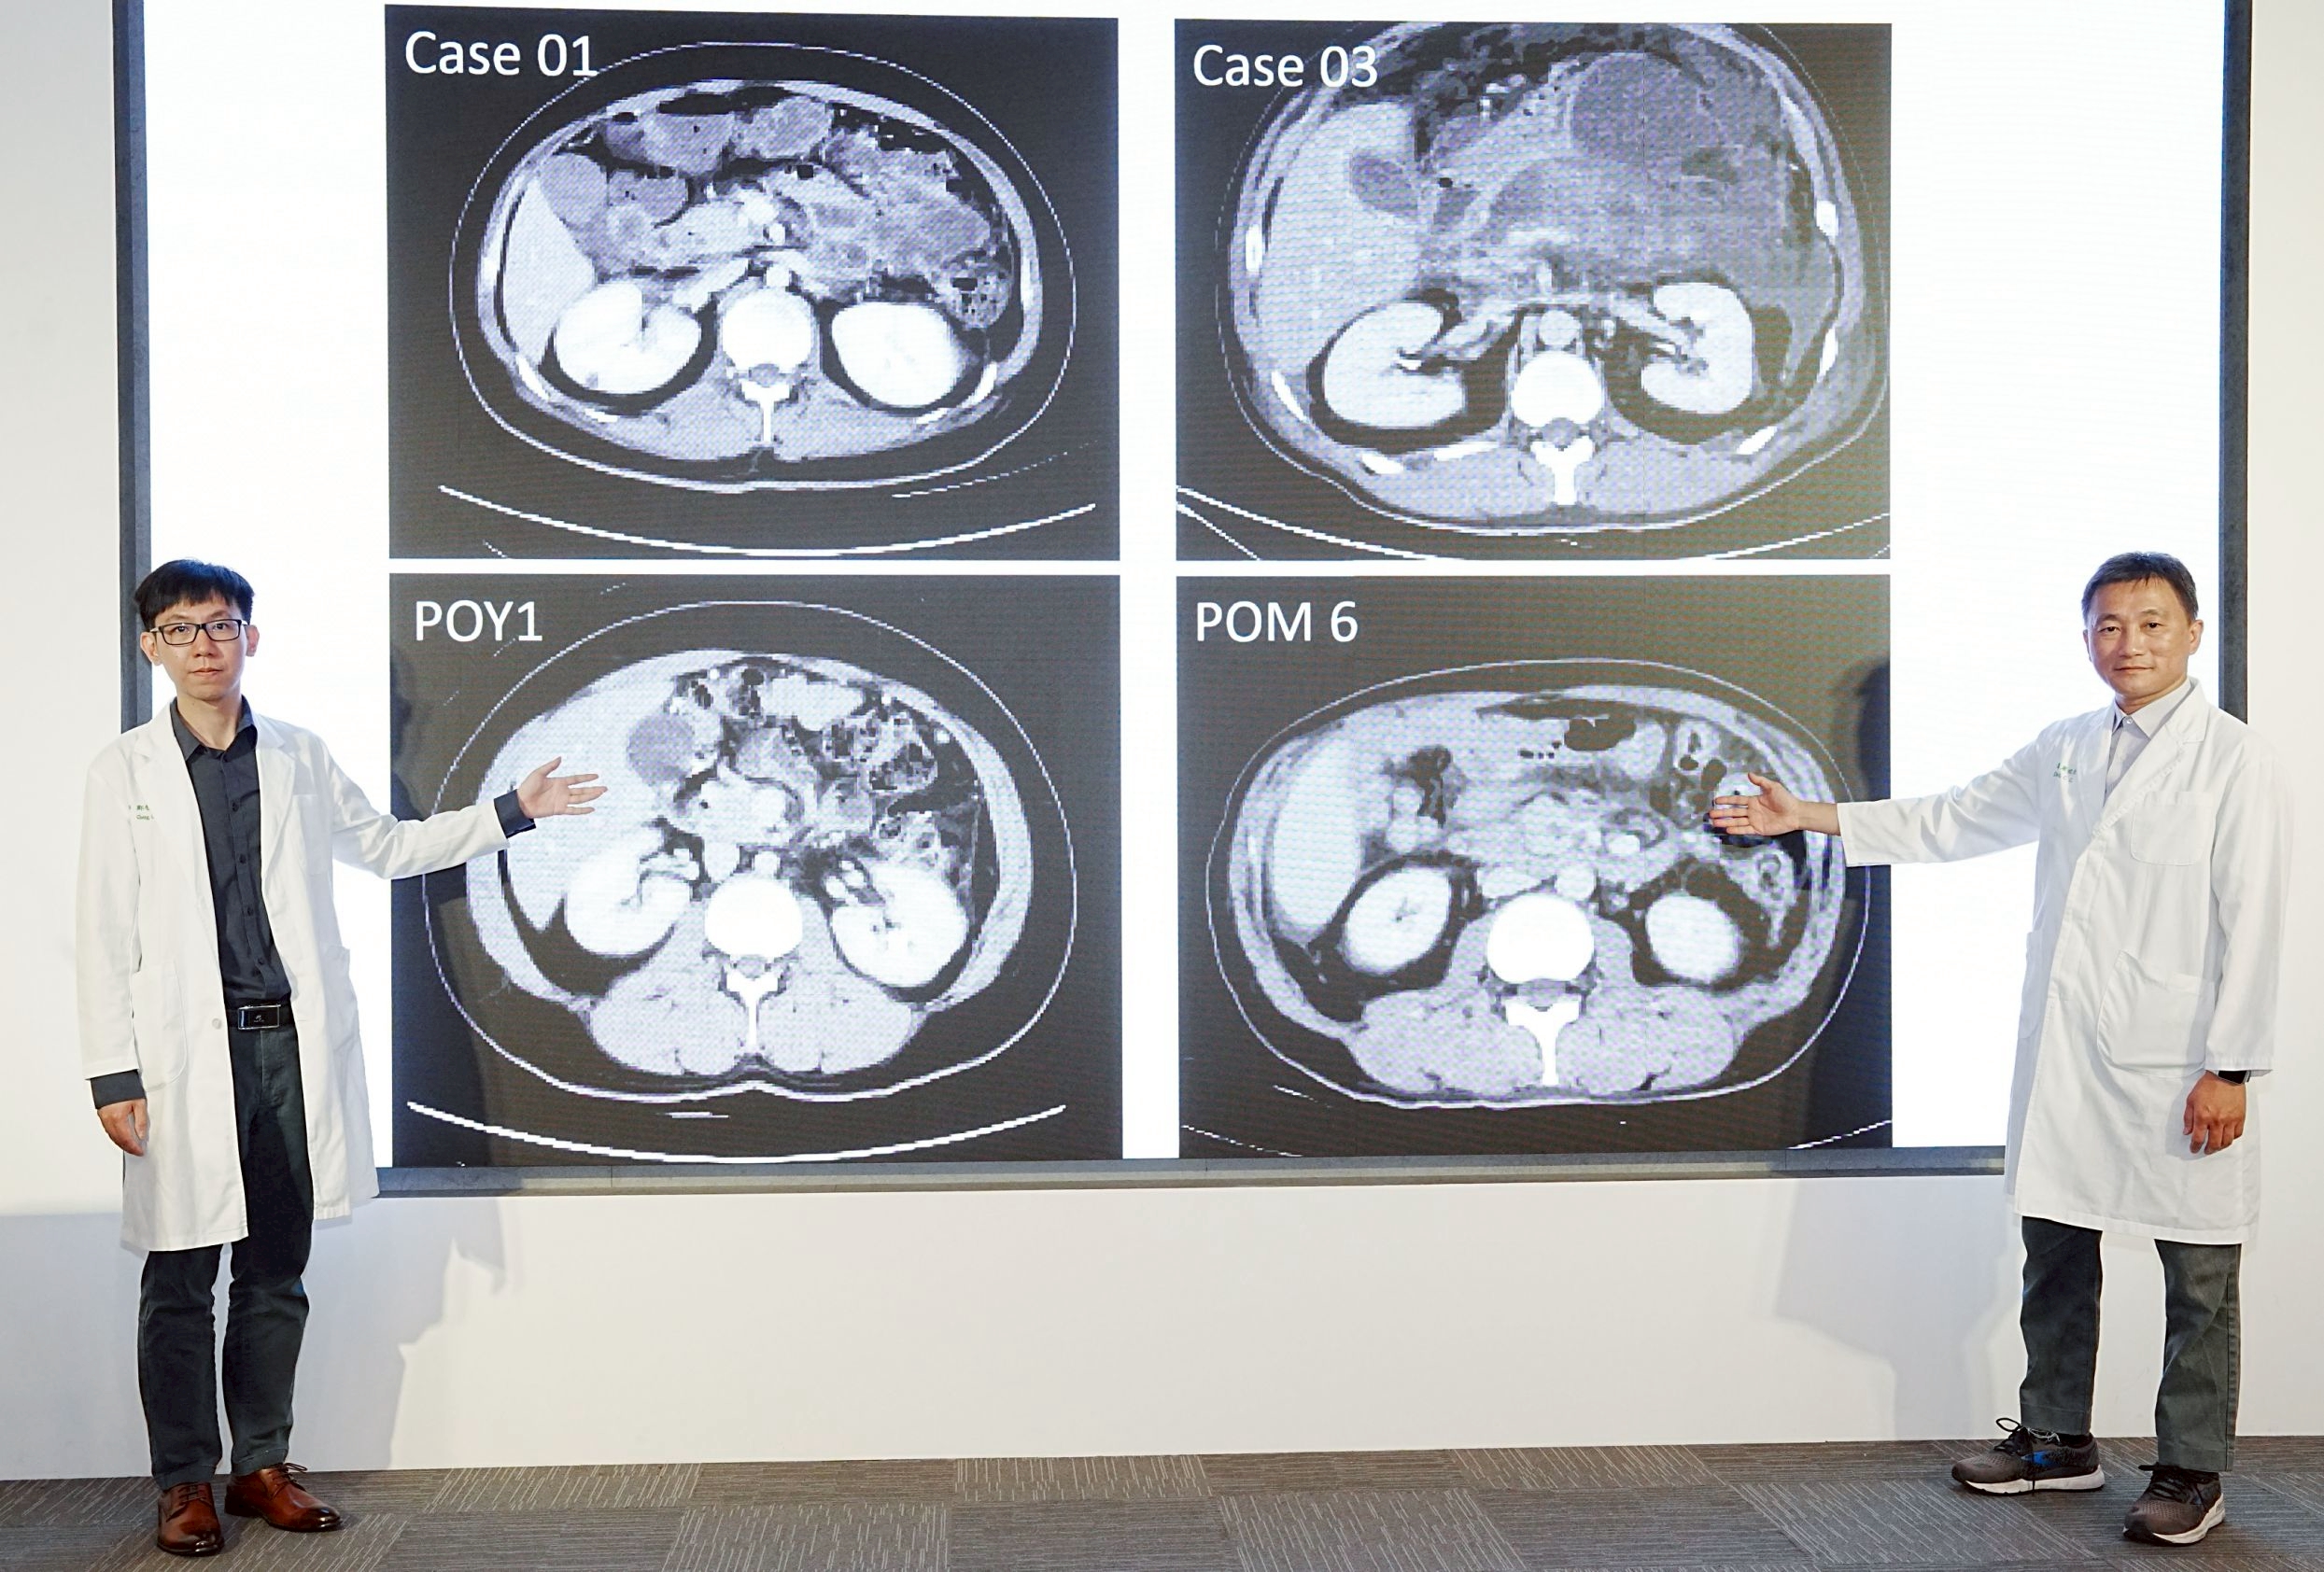

圖:一般外科葉俊杰醫師(右)表示壞死性胰臟炎的病人約70%來自膽結石的發生,請民眾需更加留意膽結石發生後的介入治療時機,鄭智忠醫師(左)也強調壞死性胰臟炎病程變化大,病人需配合多專科醫療團隊耐心治療

圖:一般外科葉俊杰醫師(右)表示壞死性胰臟炎的病人約70%來自膽結石的發生,請民眾需更加留意膽結石發生後的介入治療時機,鄭智忠醫師(左)也強調壞死性胰臟炎病程變化大,病人需配合多專科醫療團隊耐心治療

圖:一般外科葉俊杰醫師(右)表示壞死性胰臟炎的病人約70%來自膽結石的發生,請民眾需更加留意膽結石發生後的介入治療時機,鄭智忠醫師(左)也強調壞死性胰臟炎病程變化大,病人需配合多專科醫療團隊耐心治療

圖:一般外科葉俊杰醫師(右)表示壞死性胰臟炎的病人約70%來自膽結石的發生,請民眾需更加留意膽結石發生後的介入治療時機,鄭智忠醫師(左)也強調壞死性胰臟炎病程變化大,病人需配合多專科醫療團隊耐心治療經由一般外科、消化內科與放射診療科多專科團隊採取階段性治療後,其中5名病人已順利康復出院,另2名病人持續追蹤治療中,整體存活率較傳統治療方式明顯提升。